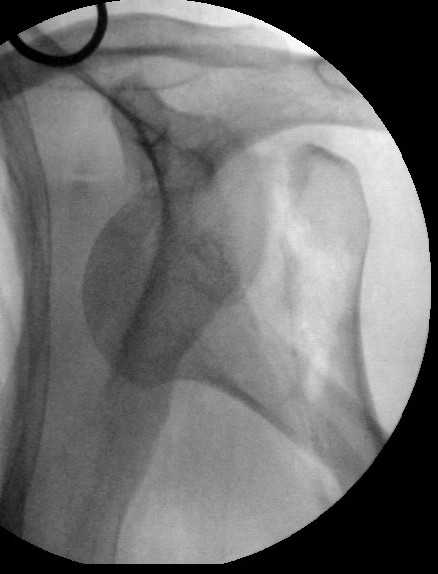

Мужчина 44 л. упал с крыши дачи 6 августа. Картиник в приложении. Лет

5 назад нде-то оперирован по поводу привычного вывихв этого же плеча.

После операции не вывихивал до этой травмы.

Как тут лечить? Есть ли шансы на закрытое вправление? Чем лучше

фиксировать? Какие меры принять с учетом бывшего и нынешнего вывиха?